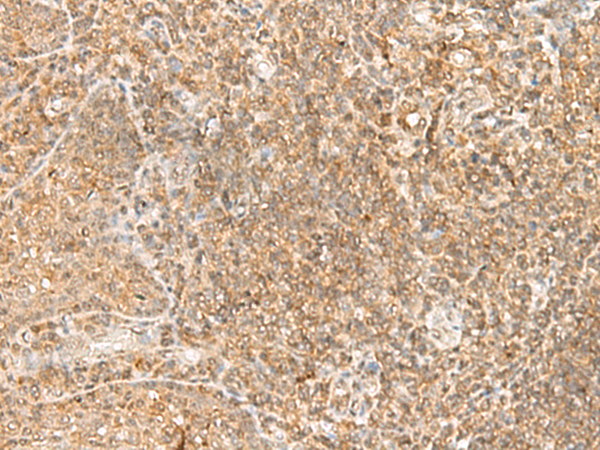

分类: 科研抗体货号: P10655别名: RAY, H-ray, RAB1C应用: IHC反应种属: Human, Mouse, Rat